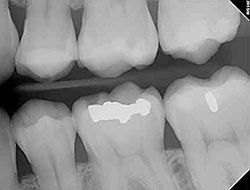

Digital X-rays

Using the most advanced dental technology is just as important as staying up-to-date on the latest treatment techniques. Because our practice is dedicated to providing you with the safest and most convenient treatment options available, we utilize advanced digital X-ray technology in our office.

Digital X-rays provide several advanced imaging options that are designed to save time, provide clearer dental photos, and expose patients to less radiation than traditional X-ray technology.

Our practice is focused on making your dental experience as comfortable as possible. At your next appointment, we’ll be happy to answer any questions you may have.